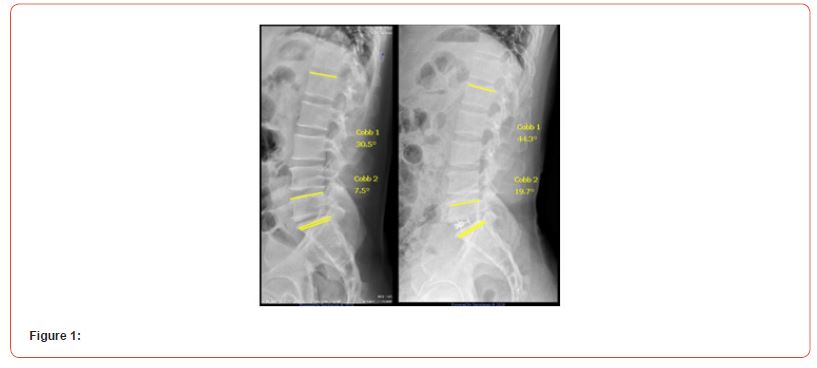

The study included patients aged between 18 and 80 years, who presented with degenerative spinal diseases and underwent surgical treatment using the ALIF technique. Only cases subjected to 1 level of arthrodesis, performed in a stand-alone manner (without posterior supplementation with pedicle screws), and who had a minimum radiographic follow-up of 12 months after surgery, were selected. Exclusion criteria were patients who required any type of revision surgery, those who developed surgical site infection, those who experienced cage subsidence, and those who did not have adequate radiographs for the evaluation of total lumbar lordosis (LL) or segmental lordosis of the operated level. The procedures were performed by 06 spine surgeons who are members of the Brazilian Spine Society, experienced in the technique, and by 3access surgeons. Neither the orthopedic surgeons nor the access surgeons were the same across all surgeries. Radiographic evaluations of segmental lumbar lordosis of the operated level (L4- L5 or L5-S1) and total lordosis (L1-S1) were performed. The COBB technique was used for these measurements (Figure 1).